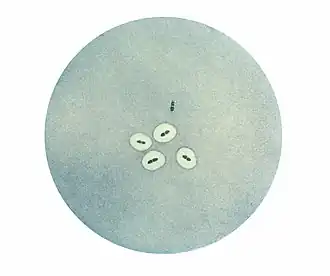

Observé au microscope, le pneumocoque se présente sous forme de diplocoques à Gram positifs lancéolés accolés par leur côté pointu, formant un chiffre 8. Dans les produits pathologiques, les pneumocoques pathogènes sont entourés d'une capsule bien visible[2].

La présence de diplocoques capsulés (dans le crachat rouille de la pneumonie lobaire, le liquide cérébrospinal, dans des hémocultures, du pus de sinusite...) permet un diagnostic d'autant plus sûr et précis que les germes sont abondants et constituent l'unique flore observée.